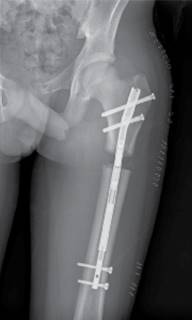

Todos los pacientes fueron instruidos para el correcto funcionamiento del dispositivo y comenzaron el alargamiento femoral a la semana de la intervención en torno a 1 mm/día. El primer control radiográfico se realizó a los siete-10 días de la intervención y posteriormente, de manera sucesiva, cada dos semanas hasta el final del alargamiento (Figura 3), cuantificando el mismo en cada revisión. Después se realizó un seguimiento mensual durante la fase de consolidación (Figura 4), la cual comprende desde el final del alargamiento femoral hasta la consolidación ósea de la zona alargada (Figura 5). Por último, se realizaron controles a los seis meses, al año y a los dos años de la cirugía.

La dismetría prequirúrgica medida fue de 38 ± 2.7 mm. El alargamiento final medido en las radiografías postoperatorias fue de 41 ± 7.5 mm. La precisión media fue de 108% y la tasa de distracción de 0.9 ± 0.4 mm/día. El índice de distracción medido fue de 13.9 ± 5.1 días/cm y el índice de consolidación de 26.6 ± 9.1 días/cm. El tiempo medio de distracción fue de 57.6 ± 25.9 días. Los datos por pacientes quedan reflejados en la Tabla 2.